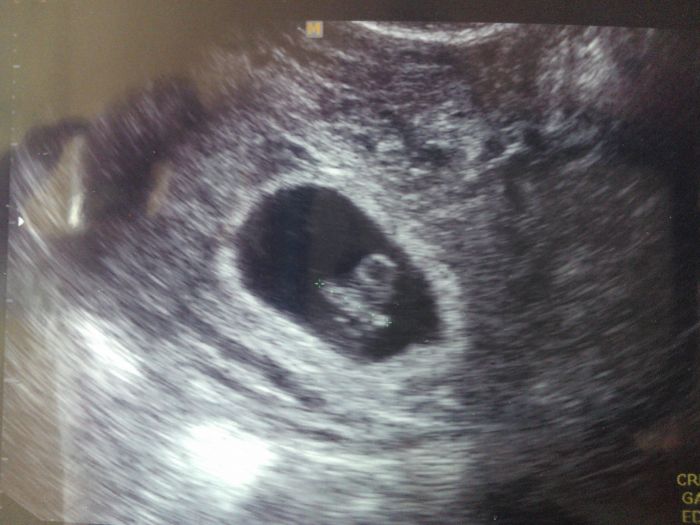

Holkyyyy, dnes podle poslední MS 7tt+4, podle ultrazvuku 7tt+0 +- 5 dní (UTZ není prostě přesný) CRL jsme měli dnes 9,86mm ...... Vše je v pořádku, a už mám i průkazku...:-)

[574794] Luci, nadherna fotka!!!!!